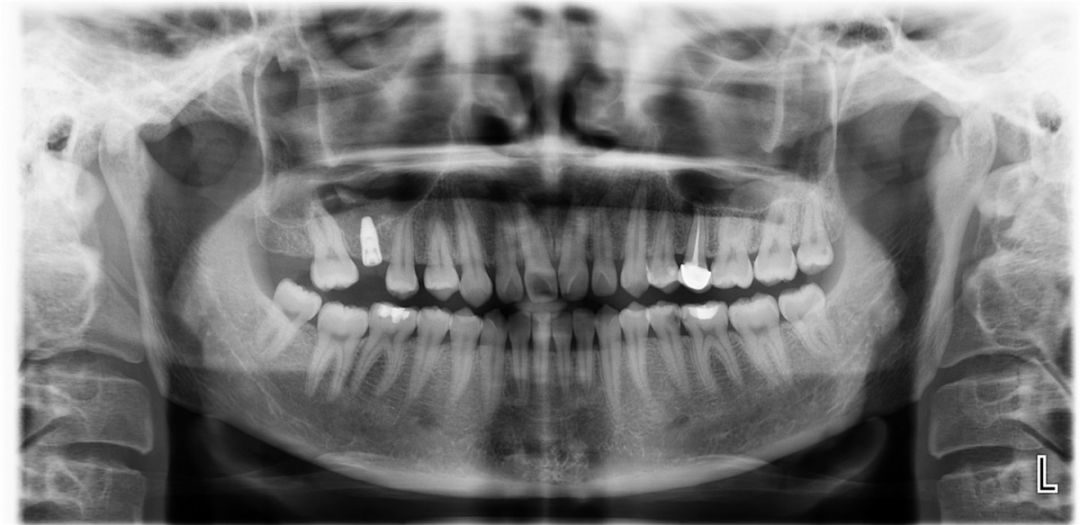

术前